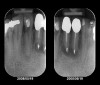

Six months later, the periodontist prepared osteotomies and placed three 3.25-mm x 13-mm implants using a vacuum-formed surgical guide fabricated by the restorative dentist (using a cast of the provisional bridge as a guide, as described by Block et al16); healing abutments were placed simultaneously. A post-implant radiograph confirmed good implant alignment with the pontics of the provisional from teeth Nos. 22 through 28 (Figure 6).

After the zirconia abutments were torqued to 20 Ncm, cotton and composite were used to cover the screw access openings. Figure 7 and Figure 8 show the finished feldspathic porcelain crowns on implants in sites Nos. 24 through 26, and on teeth Nos. 22, 23, 27, and 28; all crowns were cemented with dual-cure resin cement. Good remodeling of gingival architecture is also apparent in Figure 7. As predicted, the free gingival margin (FGM) on No. 23 is approximately 2 mm coronal to those of the adjacent implant crowns on Nos. 24 through 26 (Figure 7); as per the patient’s initial statement, this discrepancy was not an esthetic concern to her. Figure 9 shows the final post-restoration periapical view.

Figure 6  Confirmed ideal implant alignment with pontics in provisional bridge from Nos. 22 through 28—post-placement periapical view.

Figure 6

Figure 9: Implants supporting zirconia abutments and crowns, site Nos. 24 through 26—periapical view.

Figure 9